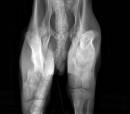

Marvin may be nine months old, but his body looks like a two-month-old puppy.  We were shocked he was alive based on his body score being 1 out of 9 which means he has been starved and is emaciated.  This little pup has literally wasted away to nothing and is now crippled because of it.  In addition to being starved, sweet Marvin has two fractured front legs.  We are assuming he was hit by a car and the family did not get him medical care.

His wrists have almost completely collapsed from lack of nutrition.  His bones had fused together and re-modeled in an angular way that tells us he was put in a kennel when he was much younger and he outgrew the area.  His legs adapted to the small space by collapsing while they healed.   This poor pup is a total mess.  The pain he has endured is unimaginable.  Marvin has learned to hobble on his rear legs while his front legs healed and collapsed all at the same time.

My Heart breaks for the suffering dear Marvin has endured.  He is as sweet as can be and petrified at the same time.   We have to get custom splints made for his legs and allow his body to regain the strength and nutrients he needs to hopefully correct his carpal area on all four legs.  We cannot do any surgery until he gets well.  We are doing everything we can to get him stronger and not bring on ReFeeding Syndrome.